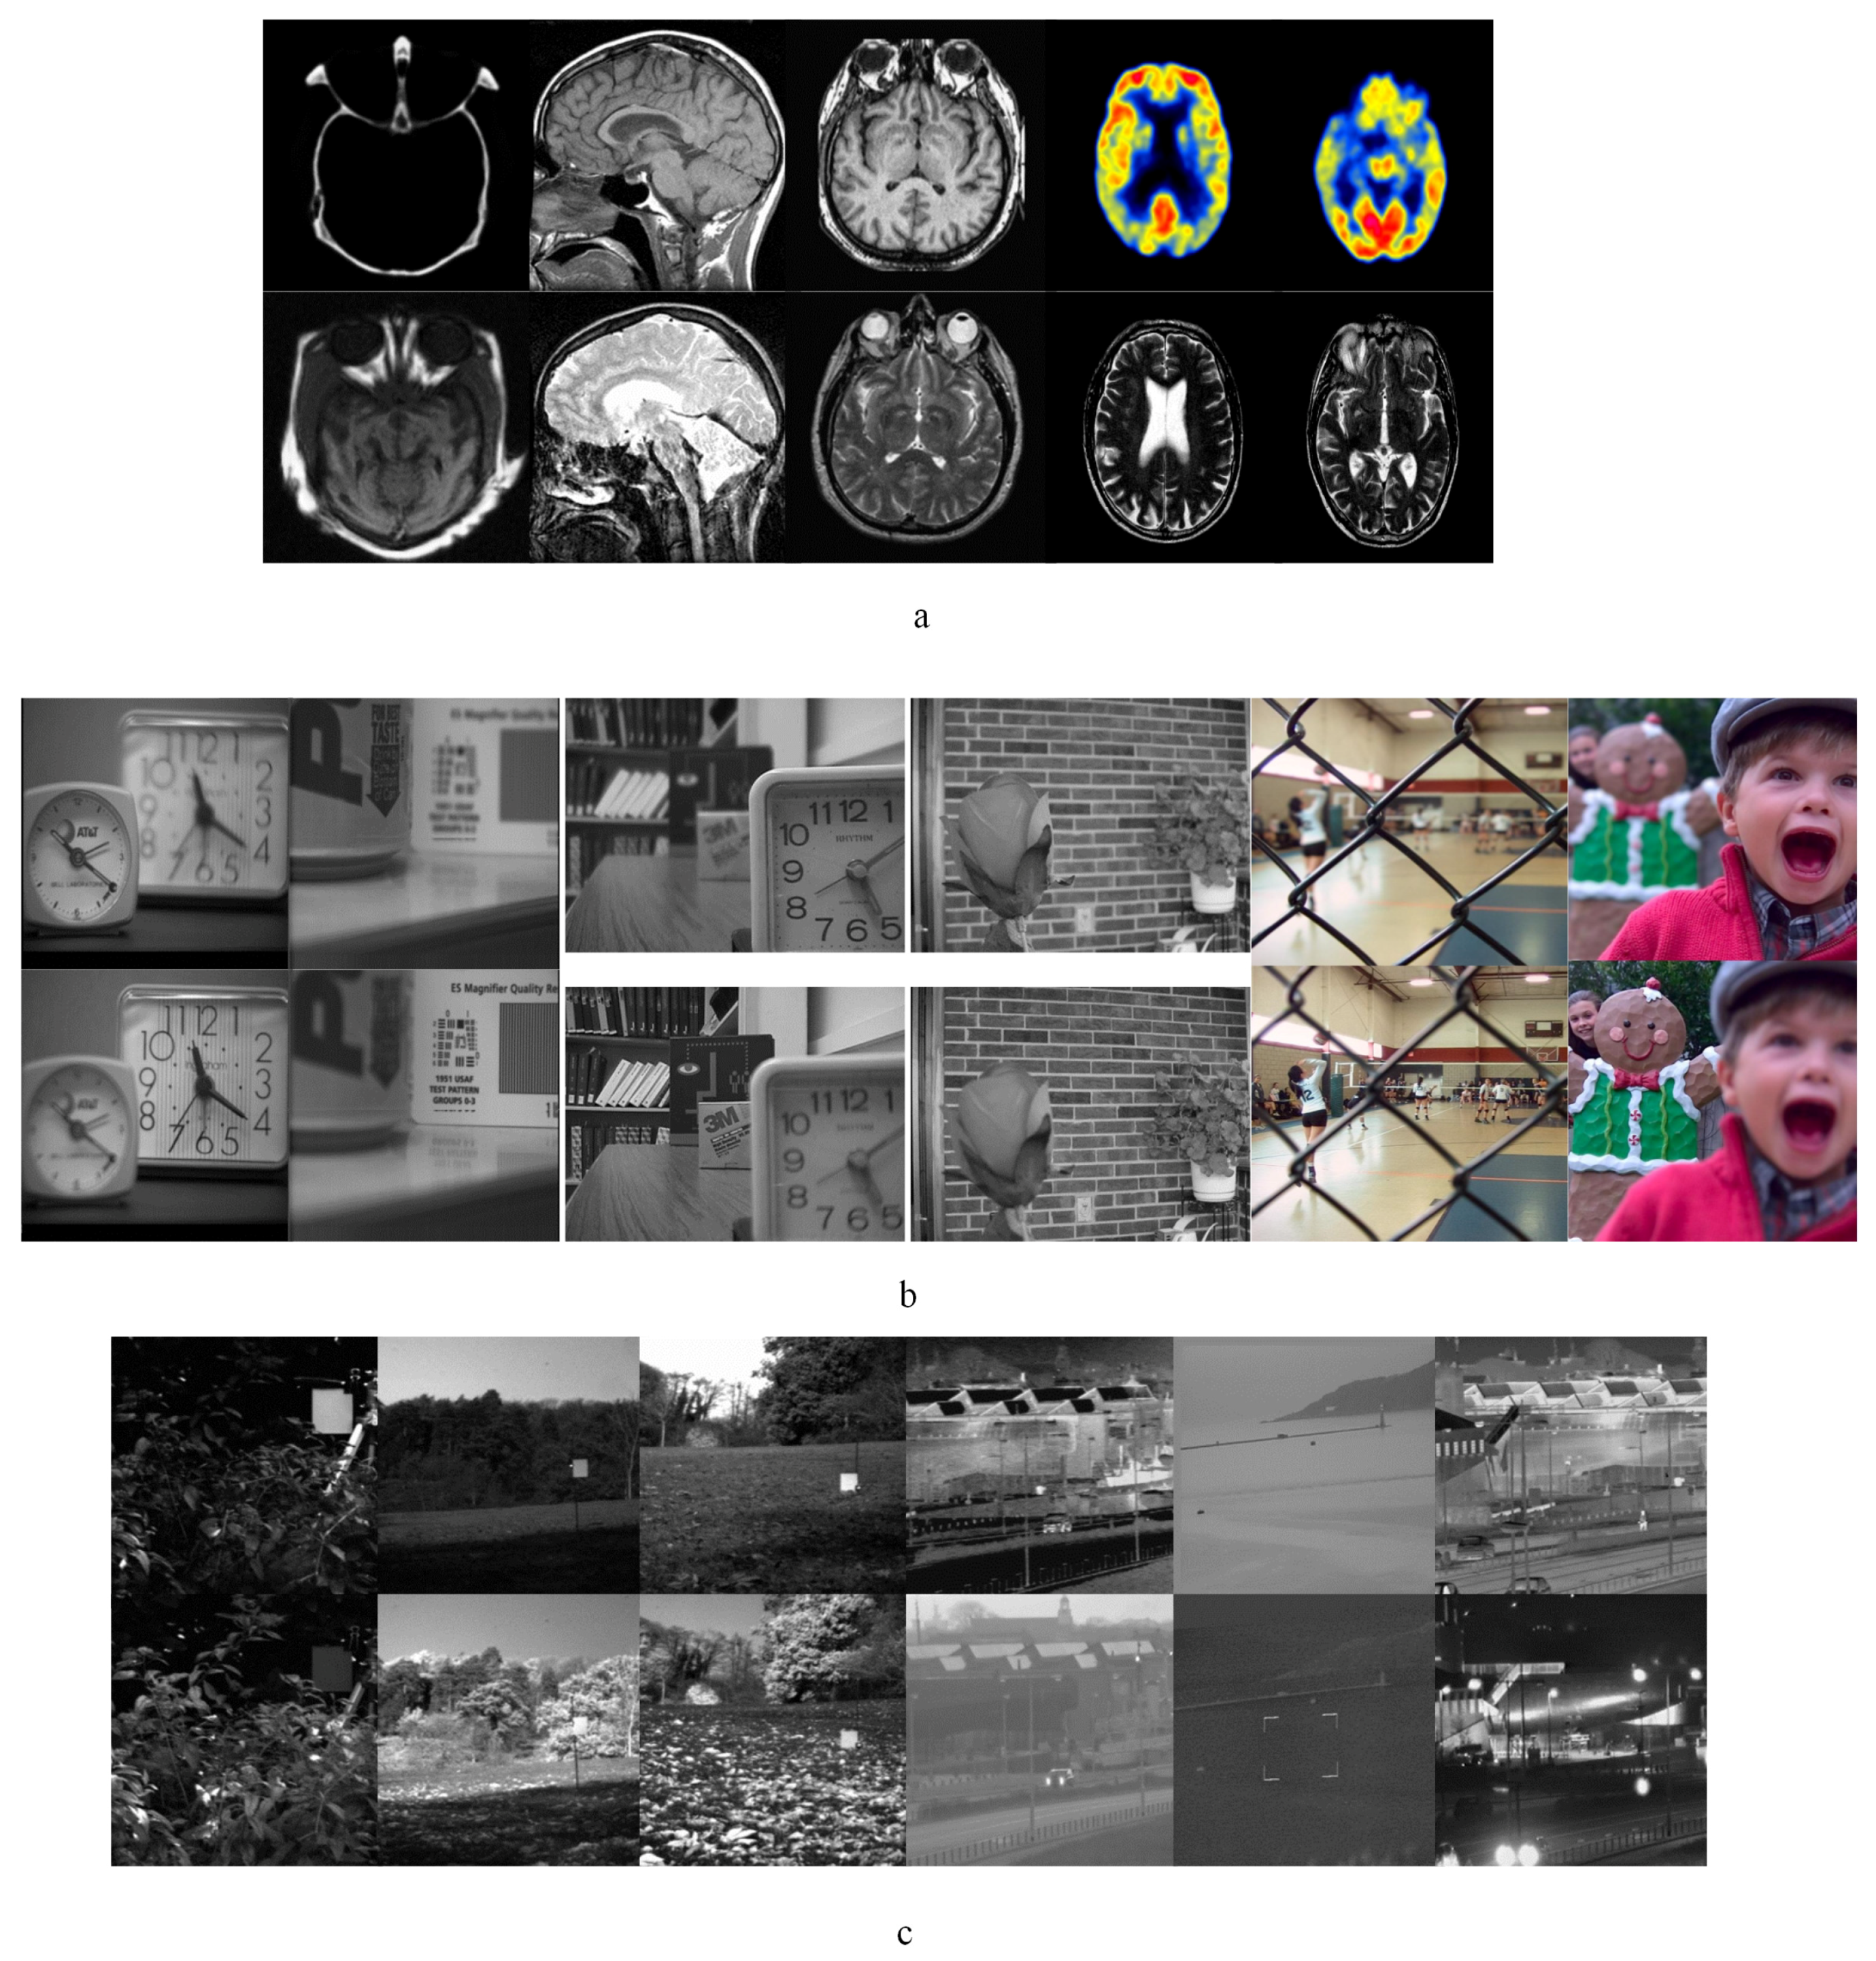

3.2.1. Experiment Results of Medical Images

3.2.2. Experiment Results of Multi-Focus Images

3.2.3. Experimental Results of Infrared-Visible Images